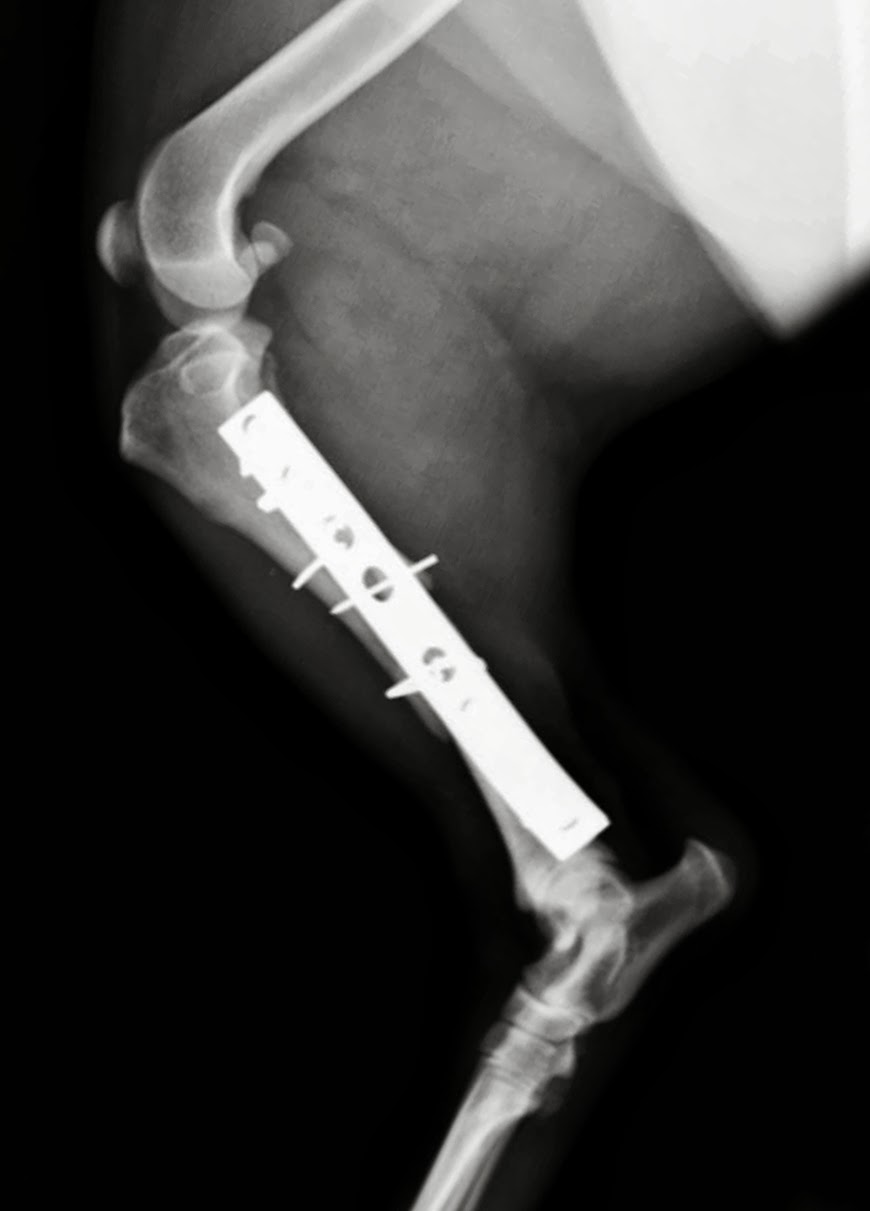

Tras la

cirugía, haremos las correspondientes radiografías de control, que expongo a

continuación, en primer lugar la vista medio lateral:

Y esta

sería la imagen post operatoria que se corresponde con la vista radiográfica antero posterior del mismo paciente:

Comprobamos

que la reducción de las fracturas es buena, la articulación tiene congruencia,

los implantes proporcionan una estabilidad suficiente, y si se logra un adecuado

control de la actividad del paciente, la evolución debería ser favorable.